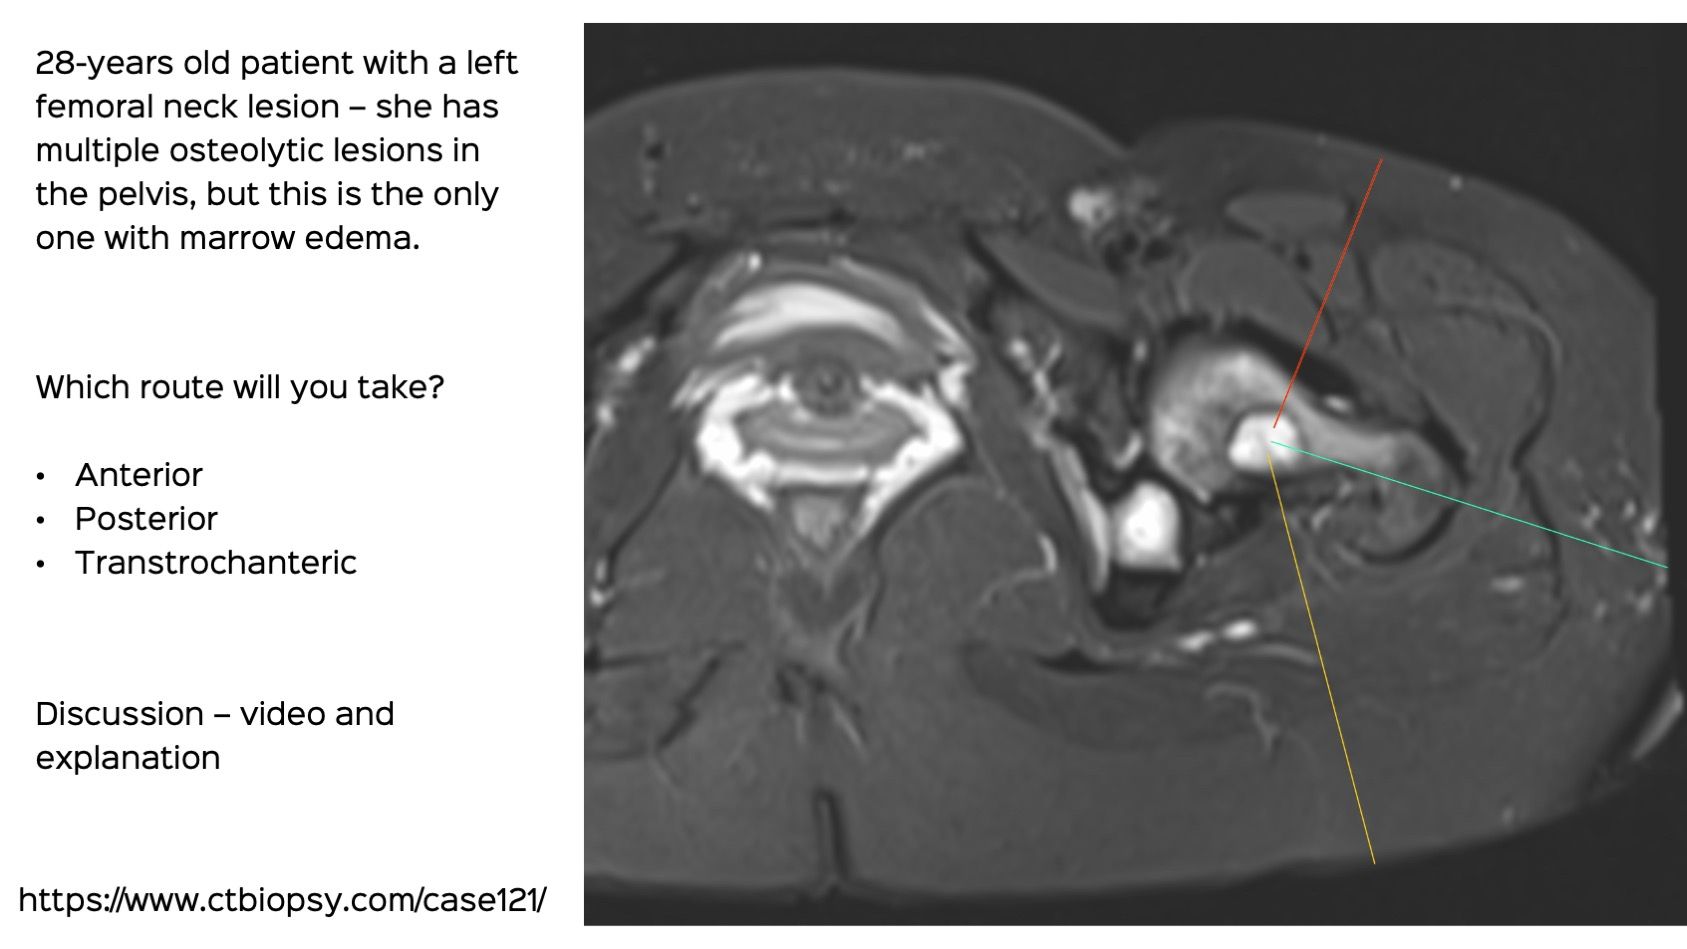

Case 121: Transtrochanteric Biopsy of a Femoral Neck Lesion